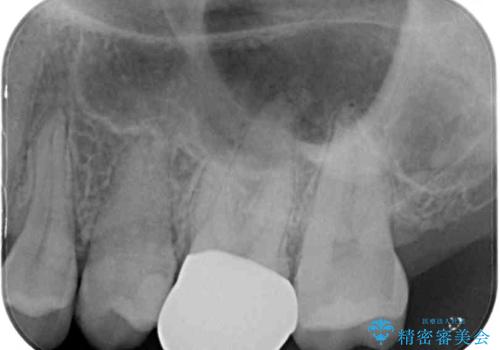

- 奥歯の銀歯の下にあるむし歯治療を希望して来院された患者様です。

口を開けたときに見えてしまう部分はセラミックインレーやジルコニアクラウンに、目立たない部分はゴールドインレーにてむし歯治療を行うこととしました。

機能面を優先すると、PGAインレー(ゴールドインレー)による修復治療やPGAクラウンによる補綴治療が望ましいのですが、笑ったときに見えている銀歯がどうしても気なってしまうとのことで、目立ってしまう奥歯はセラミックインレーやセラミッククラウンを装着することとしました。

見た目を気にすることなくむし歯治療を行うことができ、患者様に大変満足していただきました。